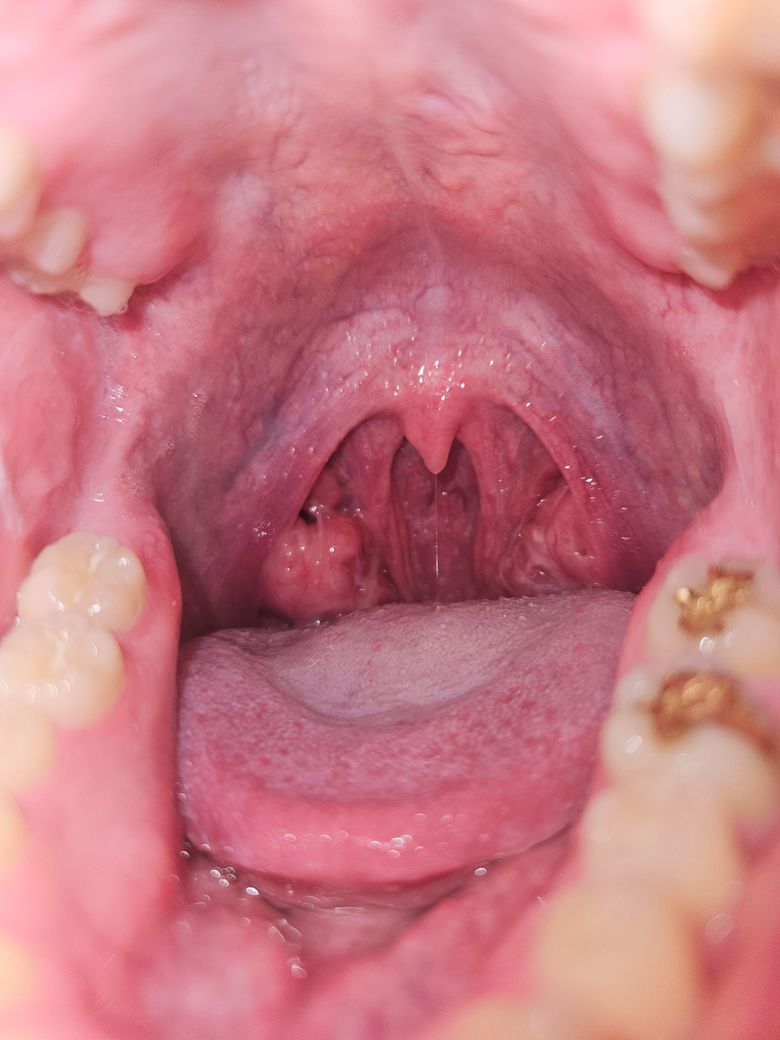

사진에서 보이듯이 오른쪽 편도에 볼록한게 보여서요, 혹시 종양일까요?

편도 결석이나 낭종도 올려주신 사진처럼 보일 수 있습니다. 이런 경우 통증 없이 몇 달간 지속되기도 합니다.